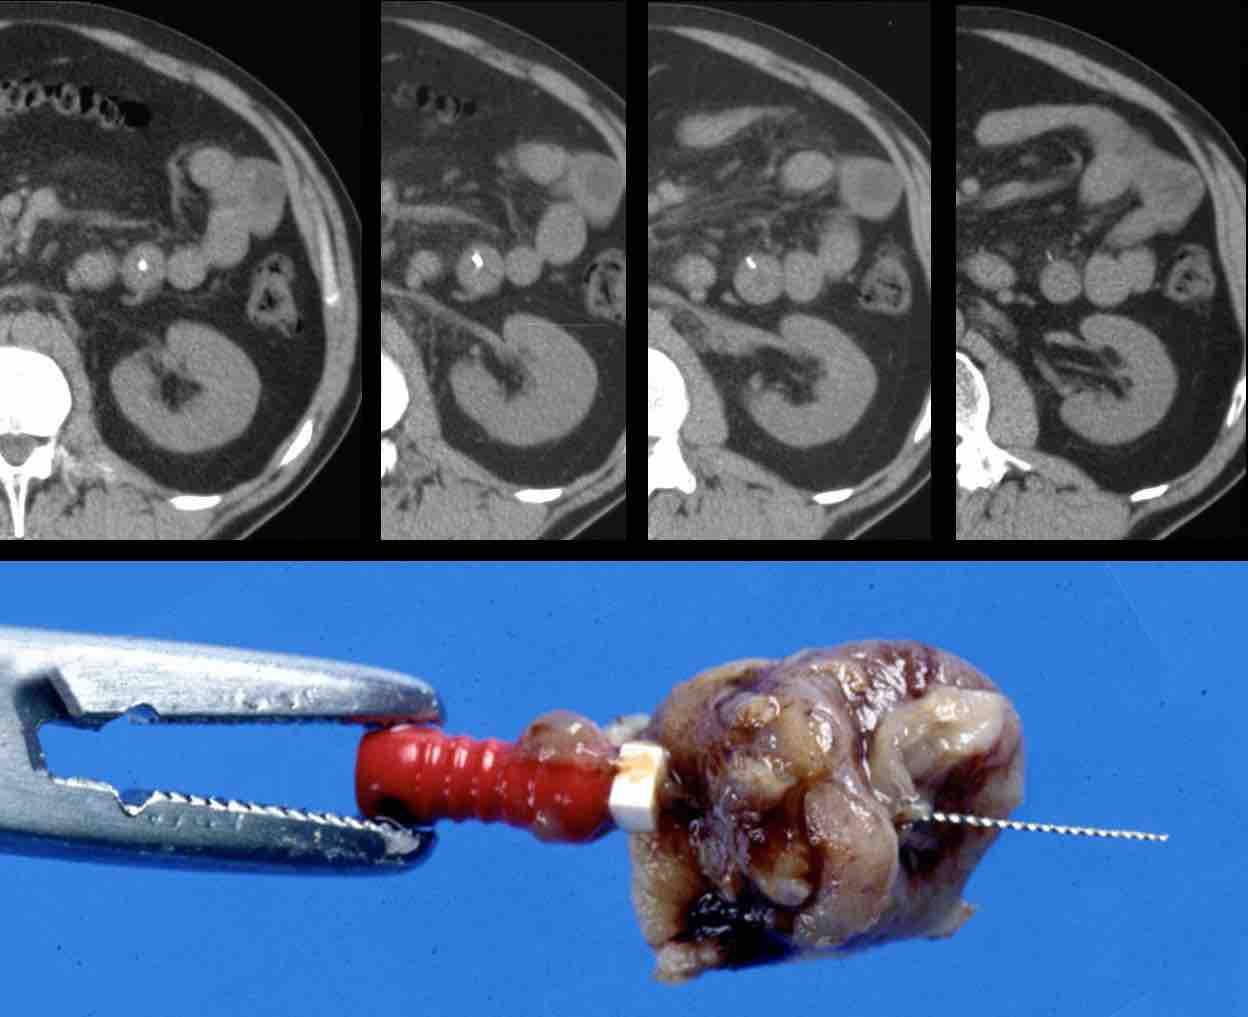

Siêu âm và CT cho thấy xương cá xuyên thủng thành dạ dày ngay trước môn vị.

Khi nội soi dạ dày không tìm thấy xương cá, mà chỉ thấy phù nề niêm mạc cục bộ với loét trung tâm (mũi tên).

Việc đưa sâu dụng cụ kẹp lớn vào vùng này cuối cùng đã thành công trong việc gắp được xương cá.